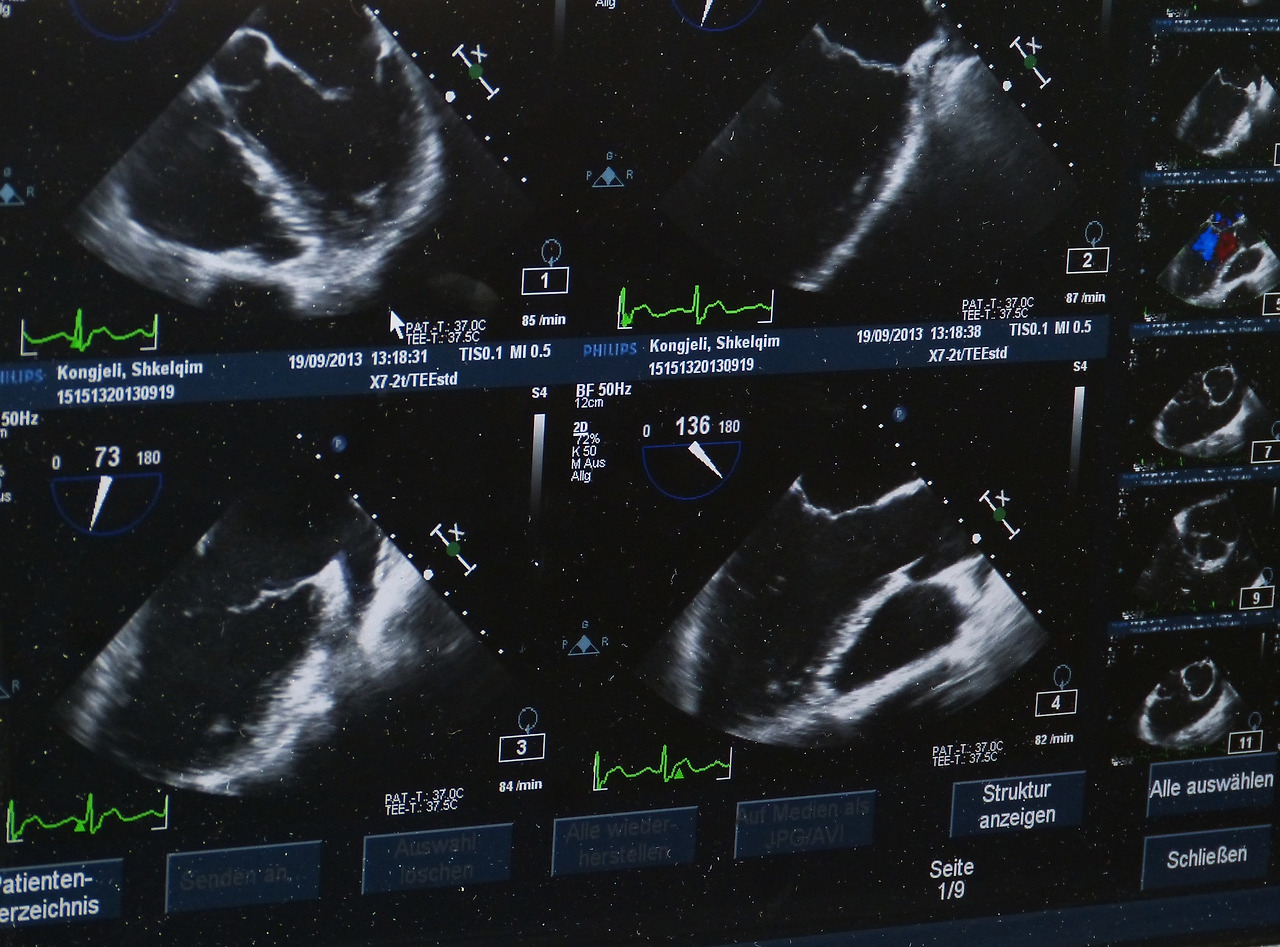

그게 뭔지 모르겠지만 초음파 화면에는 검은 장기가 하나 보였고, 그 아래로 하얗게 뭔가 끝부분에 보였다. 의사 선생님이 이게 쓸개고 그 끝을 담석이 막고 있어서 벽이 부은 거라고 하셨다. 문제의 원인을 알았다는 사실 하나만으로도 갑자기 뭔가 덜 아파지는 것 같은 기분이었다. 그렇게 초음파를 끝내고 심전도 검사를 하고 위 내시경을 하려는 찰나, 갑자기 나를 진료했던 원장선생님이 위내시경을 캔슬하고 바로 CT를 찍자고 하셨다. 뭐 일단은 아까 담석이 있다고 하셨으니 그게 맞는 것 같아서 그렇게 하겠다고 했다. 그리고 기다렸다가 난생처음 CT도 찍었다.

ultrasound-g373dbad36_1920.jpg 초음파는 아이를 확인할 때만 쓰는 게 아니었다...